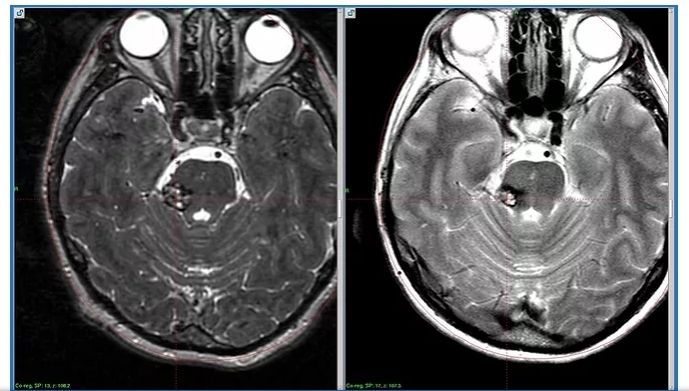

Мр картина венозной ангиомы левой гемисферы мозжечка - 96 фото